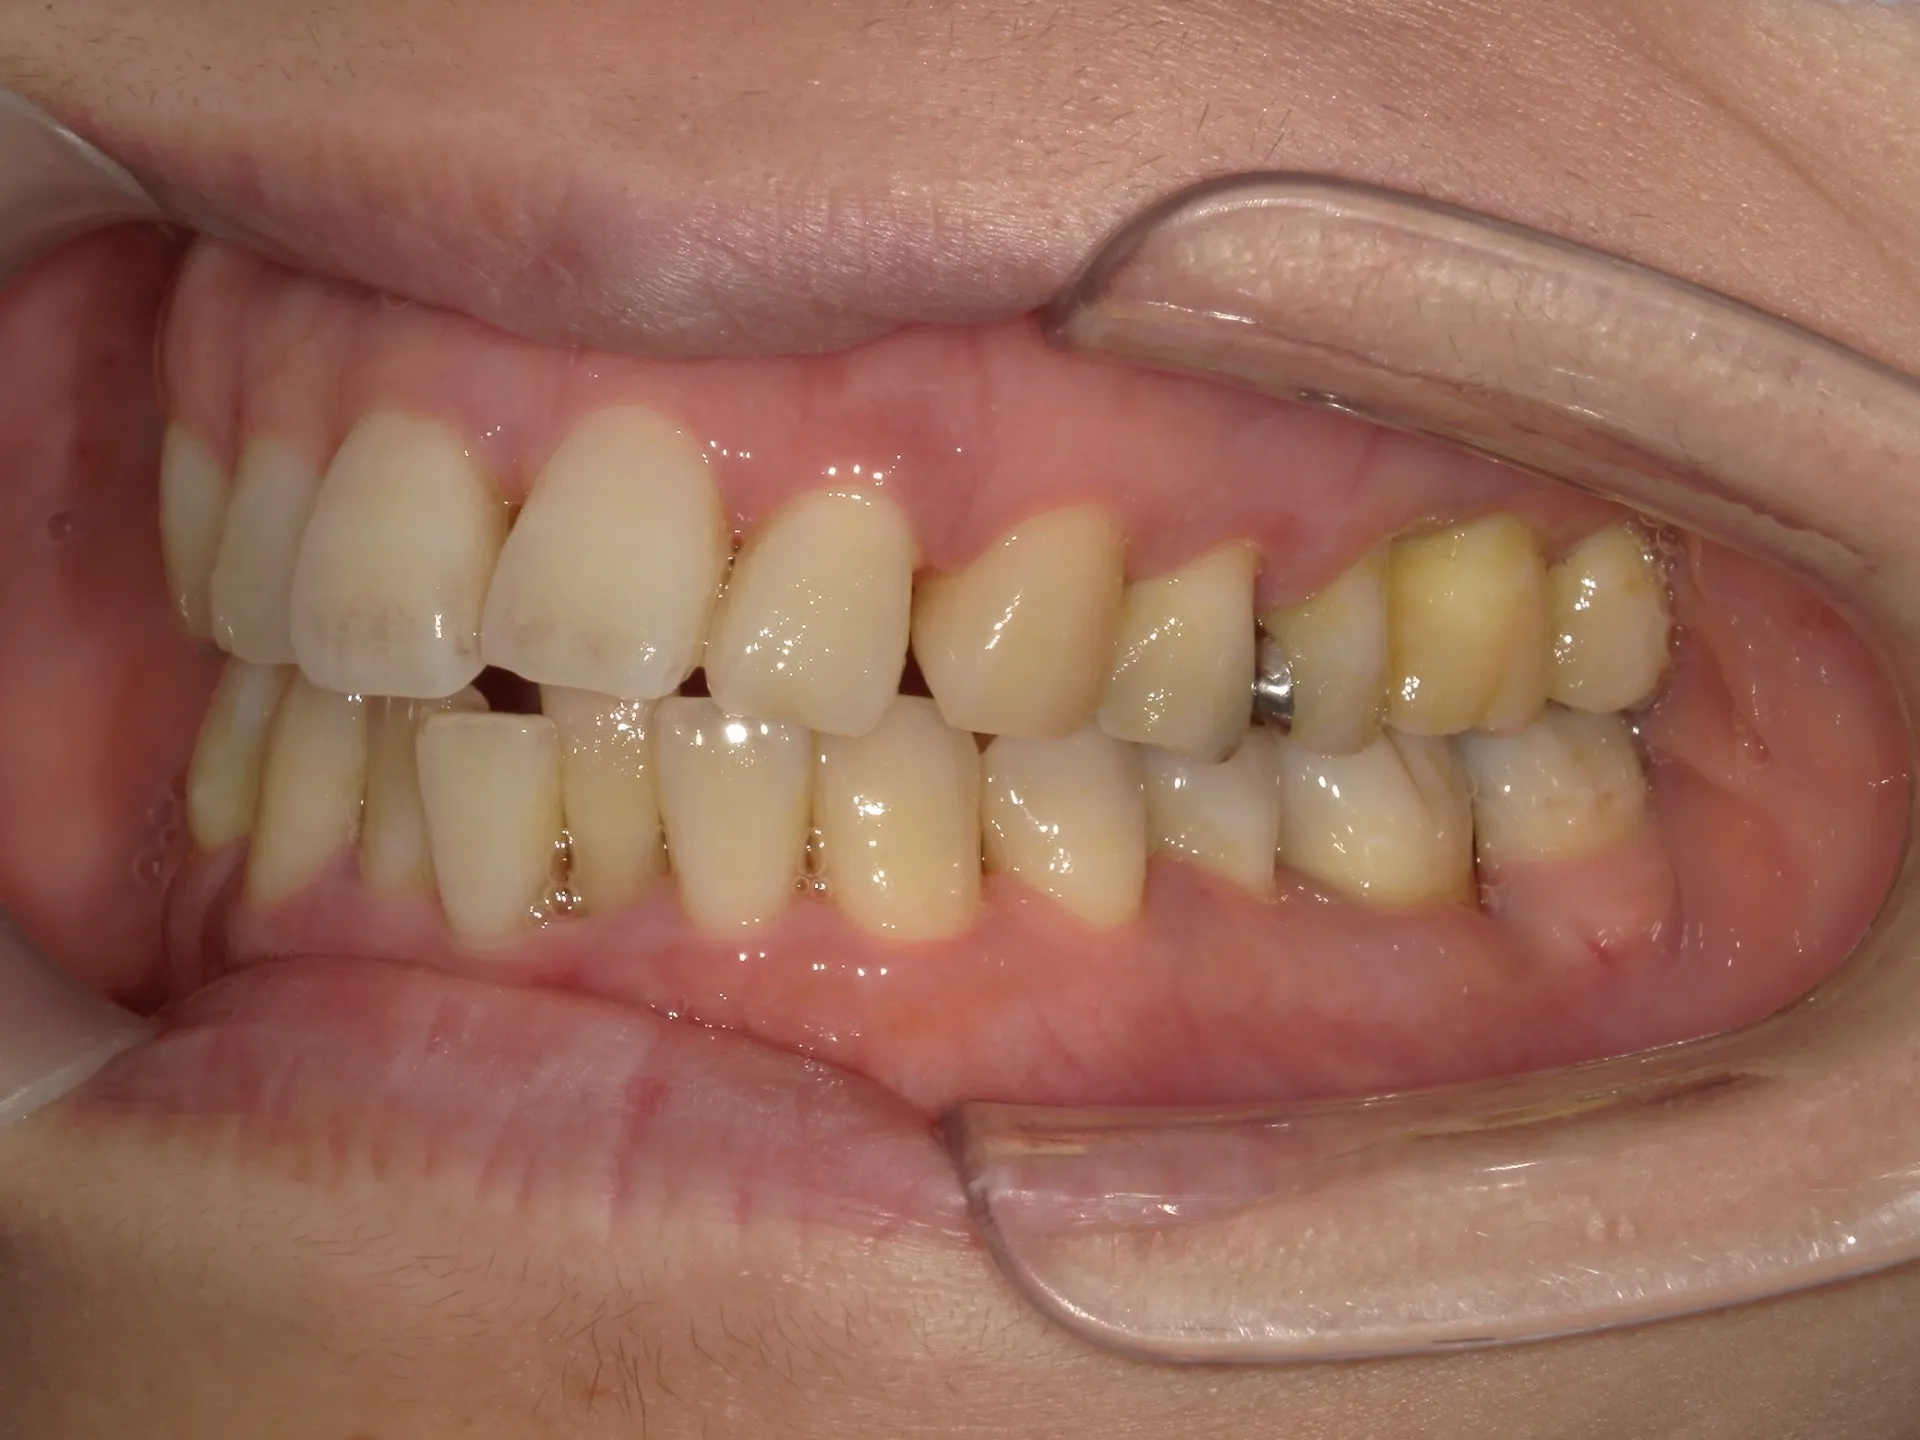

当院では矯正治療と歯周治療を平行して行うことにより矯正治療を進めていけることができました。

しかしながら、今回の治療途中で歯茎が腫れるなどの影響もあり、歯周治療中の矯正治療はリスクであることは患者様にも初回の段階で説明していることもあり、患者様もこの状態の歯並びで満足しており、歯を残すためにも今回は矯正治療を中断する希望をされました。